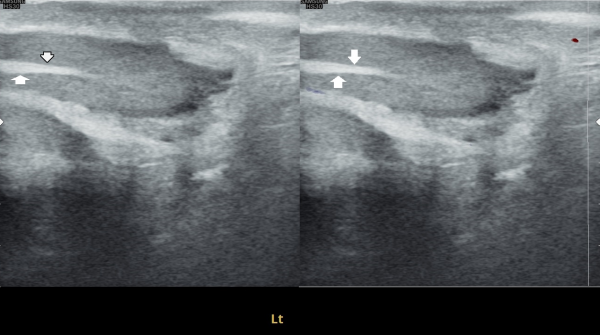

사정관과 정관등의 탈락된 상피 세포가 막혀 정자의 순환 장애를 일으키면 고환의 섬유화를 일으키는 초음파 사진입니다.

This ultrasound image shows how shed epithelial cells in the ejaculatory ducts and vas deferens can block the flow of sperm. When this circulation is disrupted, it may lead to testicular fibrosis (scarring in the testicle).

고환의 섬유화를 일으키는 있는 정관내에 막혀 있던 상피 세포 덩어리가 치료된 현미경학적 자료입니다.

This microscopic image shows clumps of epithelial cells that had been blocking the vas deferens and causing fibrosis of the testis. After targeted therapy, these blockages have been treated.